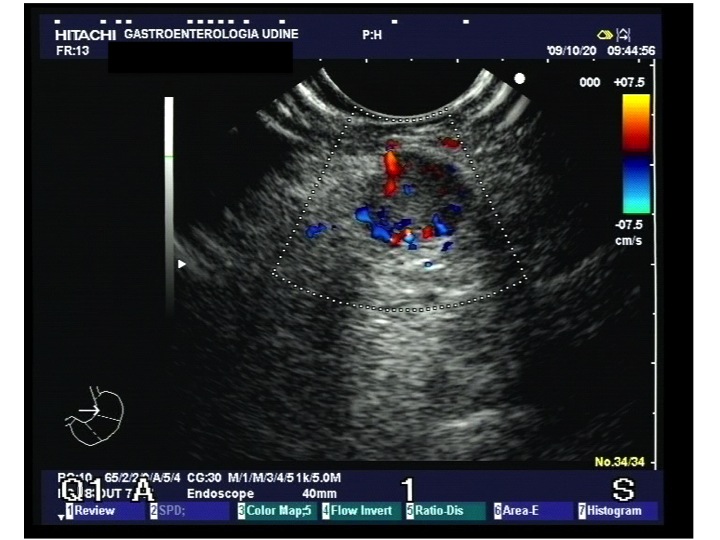

I campioni citologici, che talvolta sono l’unico materiale diagnostico disponibile, possono lasciare dei dubbi per la gestione clinica. La citologia è in grado di distinguere efficacemente i NET ben differenziati dai carcinomi neuroendocrini (NEC) scarsamente differenziati, ma la distinzione fra i tumori di grado basso e intermedio può essere impossibile. L’accuratezza diagnostica delle tecniche di aspirazione può essere limitata per le piccole dimensioni dei campioni, la riproducibilità subottimale e il rischio di possibile contaminazione da parte dei tessuti adiacenti. La citologia sta comunque conquistando un ruolo sempre maggiore nella diagnosi dei tumori duodeno-pancreatici. La tecnica di campionamento con ago sottile in eco-endoscopia è attendibile, con specificità di circa il 75%, sensibilità dell’87%, accuratezza dell’89%, valore predittivo positivo del 93% e valore predittivo negativo del 60% (2-4).